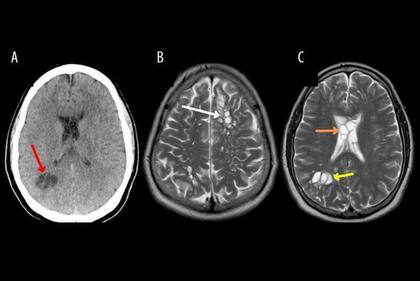

Al realizarle tomografías, los médicos encontraron la presencia de numerosos quistes en el cerebro que, según luego comprobaron con estudios posteriores, en realidad eran larvas de tenia que se habían instalado en su cerebro y que eran las causantes de una infección conocida como neurocisticercosis.

Según los Centros para el Control y la Prevención de Enfermedades (CDC, por sus siglas en inglés) de EE.UU., las larvas de tenia “entran en tejidos como los músculos y el cerebro y forman quistes. Cuando se encuentran quistes en el cerebro, la afección se llama neurocisticercosis”.